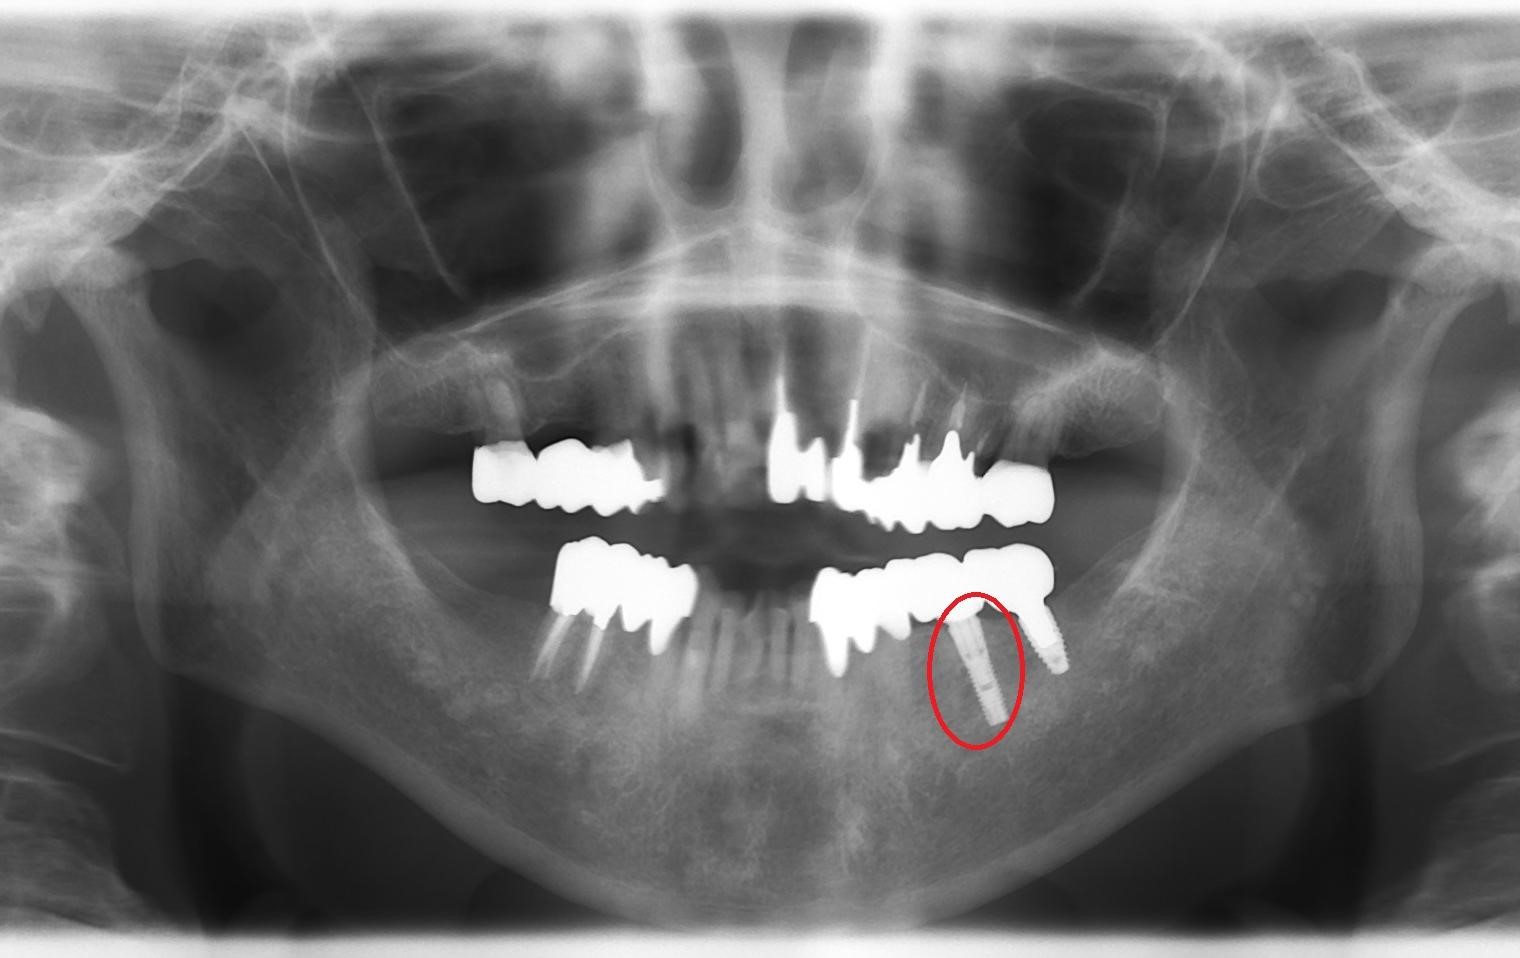

【症例】20年後も健康なインプラント(レントゲン写真)

この方は、約20年前に提携している専門医の歯科医院様からのご紹介で来院されました。「歯の根が割れてしまい、抜歯が必要」との診断を受け、失った歯を補うために当院でインプラント治療を行いました。

下の画像は、治療から20年以上が経過した現在のレントゲン写真です。

▼お口全体のレントゲン写真 赤丸で囲んだ部分が、20年前に治療したインプラントです。